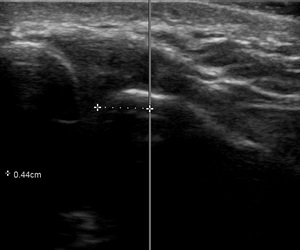

The width of the AC joint normally measures 1-6mm in females and 1-7mm in males. A joint width of <0.5mm may be considered normal in patients over 60 years old.5 The joint plane is typically slanted 20°–30°, with the clavicle overriding the acromion, however, there is significant variability in the degree of slant, ranging from nearly vertical to nearly horizontal.6 The small size of this joint makes it relatively difficult to access in one pass using a palpation-guided approach, which relies on landmark palpation. The act of walking the needle along the clavicle or acromion until it falls into the joint is painful for the patient. Moreover, there is no guarantee that the injectate is truly in the joint space using the palpation-guided approach.

Two Primary Care Sports Medicine (PCSM) Fellows who were trained in musculoskeletal anatomy and musculoskeletal ultrasound, served as the study investigators. They were supervised by a board certified PCSM Attending Physician who is also credentialled and Registered in Musculoskeletal (RMSK) sonography. One of the study investigators was asked to identify the patient’s left and right AC joint using the palpation technique and then using a pen, mark the site through which they would insert the needle. The second PCSM Fellow then centered a Fujifilm Sonosite PX 15-4 ultrasound probe over the pen mark. The distance to the nearest border of the AC joint was measured and recorded using the ‘caliper’ function in the Sonosite software to the nearest tenth of a millimeter. The investigator’s accuracy on each shoulder was not made available to them, so there was no opportunity to adapt their approach to future subjects. One Fellow marked both shoulders of a single subject while the second Fellow only operated the POCUS on that subject.

Across all subjects, the raw mean distance from the point landmarked by the investigator compared to the nearest margin of the AC joint was 8.62mm (95% CI: (8.58-8.66)). Within-subject variation in the distance measured was minimal across shoulders (Figure 4), and neither age, gender, nor BMI had any association with the distance (p=0.373, p=0.842, p=0.431, respectively).

Our study demonstrated that on average, a skilled investigator typically landmarks a space 8.6mm away from the nearest border of the AC joint and is more likely to be medial than lateral. Laterality is important, too, because the angle the joint makes is inferior and medial. Using the palpation-guided technique, a “lucky” angle is less likely to be achieved if the investigator is medial to the joint. It is worth noting that the pain experienced by the nearly 60% of patients who reported an adverse event during an AC joint injection cannot be differentiated between pain from piercing the skin or missing the joint. However, using POCUS to directly visualize the joint and the angle it makes, this landmarking error is eliminated. With a slow, deliberate approach under ultrasound guidance, the needle can be advanced between the acromion and clavicle in one steady movement. In addition, direct visualization of the injectate filling the joint space all but ensures a successful procedure, while minimizing patient discomfort.

Notwithstanding the fact that the width of a 25ga (0.52mm) needle can be greater than a normal AC joint in an elderly patient (<0.5mm), the chances of ‘blindly’ inserting a needle into a space as small as the AC joint without some manipulation is very unlikely. Each repositioning of the needle during a palpation-guided injection causes additional patient discomfort.